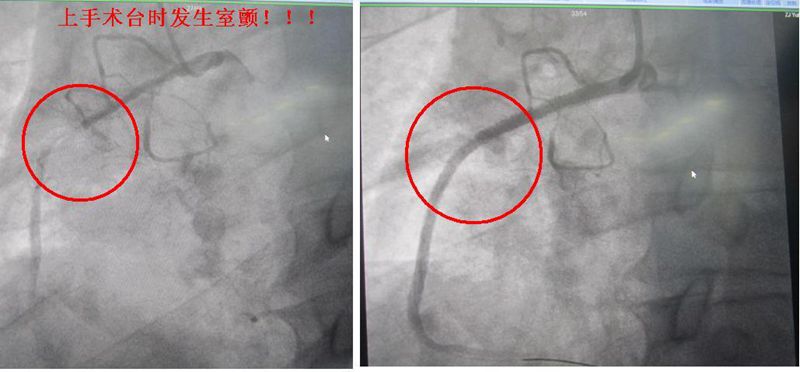

冠脉造影500例,其中急诊冠脉造影60例。开机两个月,独立开展急诊PCI术,为急性心梗病人行急诊PCI术治疗50例,6名患者发生室颤,不少患者发生了室速、停搏、低血压、休克等严重临床状况,全部抢救成功。